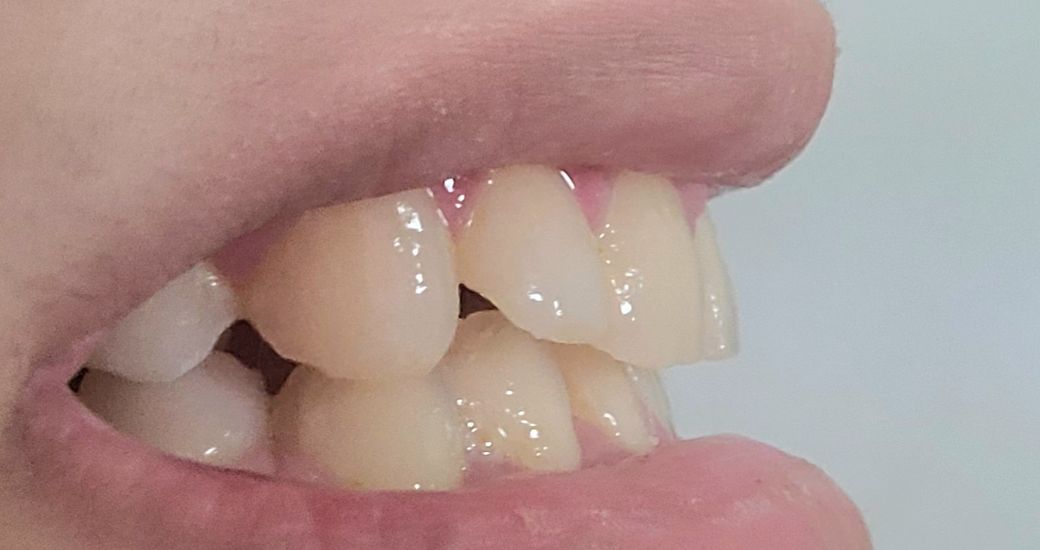

윗니 유지장치 안했는데 많이 휘었나요? (사진주의))

윗니는 고른편이고 아랫니가 심했어서 아래만 하려다가 위도 같이 하게 됐습니다. 때고 나서 아랫니는 고정된 유지장치를 했고 위는 빼고 끼는 유지장치로 받았습니다.

첫몇달은 잘끼고 다녔지만 불편하고 자주 까먹어서 이제는 전혀 안끼고 다닙니다^^... 손가락으로 치아를 문지르면 치아간의 차이는 약간 느껴지지만 개인적으로 외관상 봤을때는 다를게 없어보여요. 물론 제가 전문가가 아니라서 뭐라고 할수는 없고 제 게으름에 반성해야하지만...

• 3번 째 사진

교정이 끝났을 때 초기 상태를 알 수 없기 때문에 유지 장치를 사용하고 난 다음에 치아가 얼만큼 이동했는지 확인하기 어렵습니다.

교정을 하고 나면 치아는 교정하기 이전으로 돌아가려고 하는 속성을 가지고 있기 때문에 가능한 유지 장치는 오래 끼고 있는 것을 권고하고 있습니다.

다소 변형이 되고 있는 것으로 보이며, 유지장치를 착용하지 않는 경우치아가 서서히 움직여 변형이 오게되기에 유지장치를 잘착용하길 권합니다.